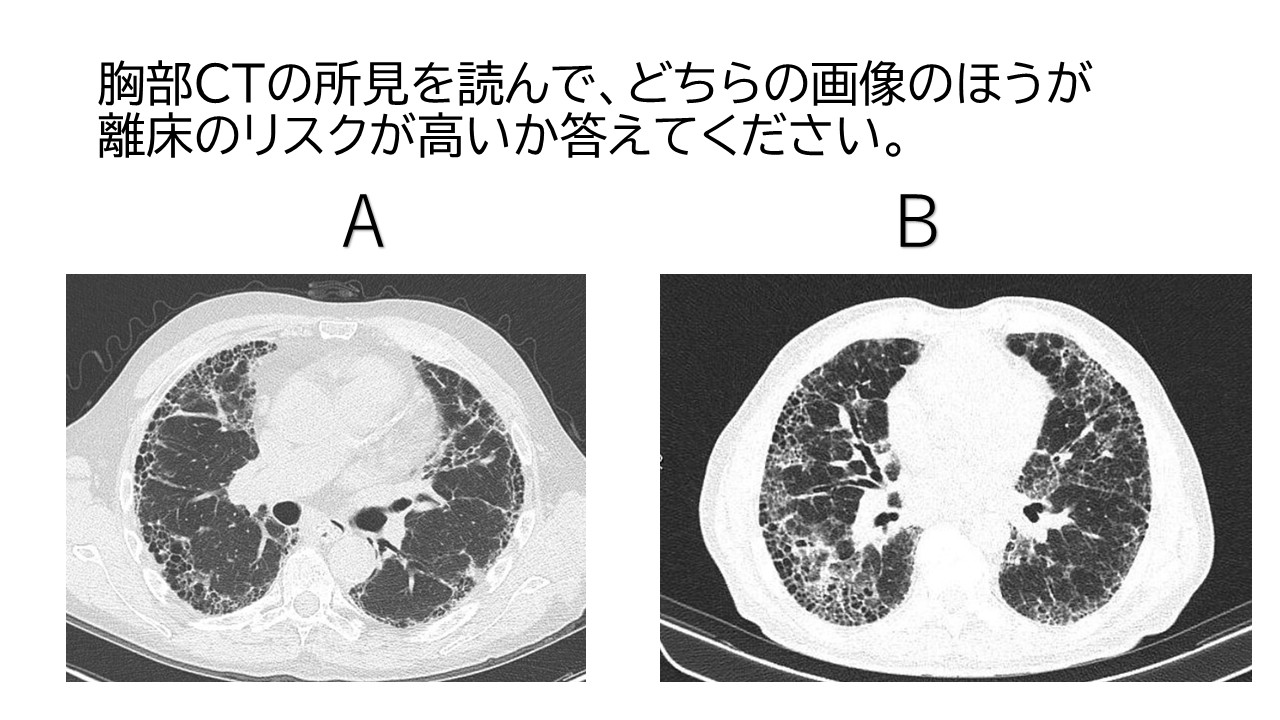

2つの画像のうち離床のリスクが高いのはどちらでしょうか?分からないという方は、下記講座の適応あり!

Bの方がリスク管理が高いと考えられる。両方とも胸膜化に蜂巣肺が広がり、牽引性気管支拡張症を認めますが、Bの方がその範囲が広範囲であるため。

※上記、肺水腫・間質性肺炎の画像判読講座では詳しく解説します。

画像提供:radiopaedia.org